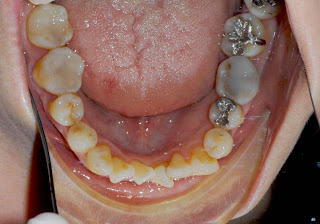

↑上の歯を、裏側から見たところです。

前歯4本は、新しい差し歯。歯の裏に金属が使われていません。

↑下の歯です。この後、一本抜歯する予定。

あごのスペースが小さいので、抜歯しないで矯正するのはむずかしいようです。